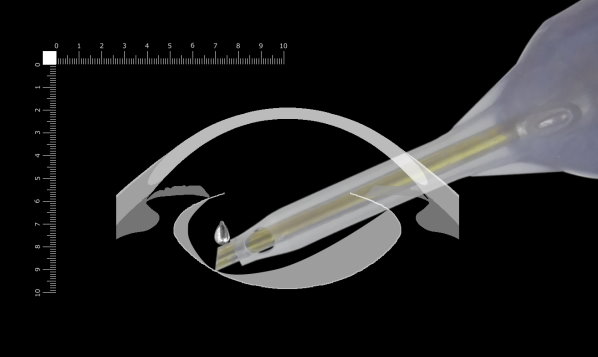

ここでは側面画像から考えます。

さらに先を見てみます。フェイコチップのベベルが垂直より手前(上)を向いている場所では掘っているところがよく見えます。チップの先端を見ながら掘っている限り大きく突き抜けることを回避できます。少し突き抜けたとしてもチン氏帯で固定されているため嚢がチップを閉塞することはありません。ここを深く掘るべきと考えます。

最も薄くなった最周辺部にチップを当て、フックは後嚢を突き破らないようにやや高い位置に当てて分割し、できた亀裂を広げていくのが最も安全で可能性の高い方法と考えます。